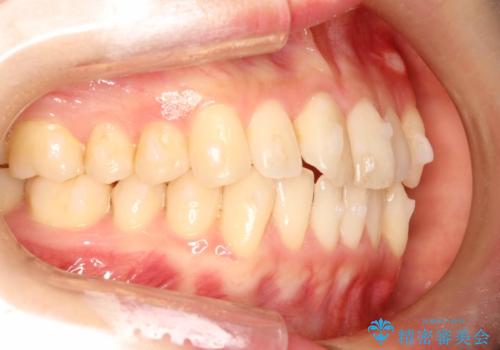

前歯のガタガタをインビザラインで目立たず矯正

- 目立たずに前歯を矯正したいとのことで来院されました。

歯と歯の間にわずかに隙間を作りスペースを確保し、インビザラインにて矯正を行うこととなりました。

前歯の微調整に少し時間がかかりましたが、整った歯並びにすることができました。